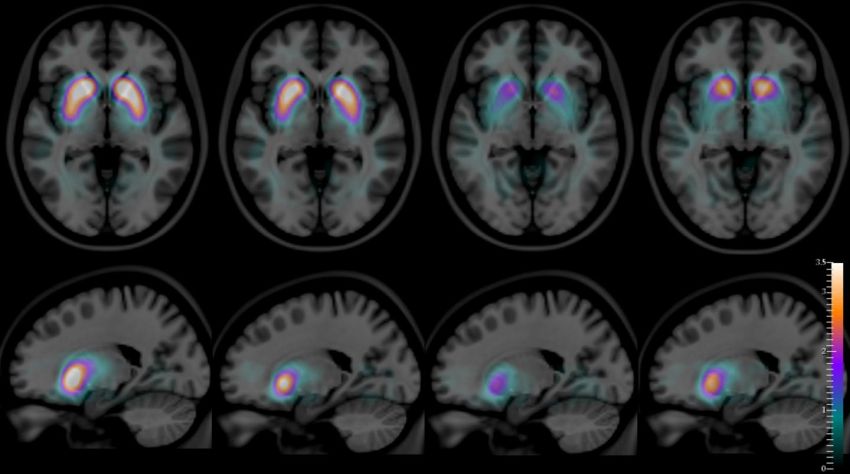

Scansioni SPECT, sovrapposte su una risonanza magnetica Atlas, di una fetta assiale (riga superiore) e una sagittale (riga inferiore) del cervello umano, con una scala di colore artificiale quantitativa che mostra le differenze nella distribuzione media del composto radioattivo [123i]FP-CIT nello striato di controlli sani, persone con Alzheimer, con demenza da corpi Lewy e con Parkinson (da sinistra a destra).

Da diversi anni, afferma Durval Costa (autore senior del nuovo studio e capo del laboratorio di radiofarmacologia del Champalimaud Experimental Clinical Research Programme) si ipotizza che l'uso di una tecnica di scansione chiamata SPECT (tomografia computerizzata a emissione di singolo fotone), combinata con l'iniezione endovenosa del composto radioattivo [123i]FP-CIT, dovrebbe consentire di distinguere la demenza da corpi di Lewy dal MA.

Ciò è dovuto al fatto che il [123i]FP-CIT si lega ai trasportatori della dopamina (un neurotrasmettitore) situati sulla membrana dei neuroni produttori di dopamina, che sono molto abbondanti in una parte specifica del cervello chiamata striato.

Dal momento che i neuroni striatali che producono dopamina sono esauriti nella demenza da corpi di Lewy (proprio come lo sono nel MP), ma non nel MA, era naturale presumere che lo schema di distribuzione di questo composto nel cervello dei pazienti, rivelato dalle sue emissioni radioattive (catturate da una fotocamera speciale), possano consentire ai medici di visualizzare la DLB, e di distinguerla in modo quantitativamente accurato dal MA.

E, per la prima volta, le autopsie confermano i dati di scansione con precisione molto elevata: le immagini ottenute consentono non solo di differenziare la DLB dal MA, ma anche la DLB dal MP (i cui modelli di distribuzione [123I]FP-CIT corrispondenti sono anche diversi da un paziente all'altro). Tornando agli anni finali strazianti di Robin Williams, è degno di nota che i suoi medici alla fine gli avevano dato la diagnosi di MP anche se lui e sua moglie erano certi che c'era qualcos'altro di molto sbagliato in lui.